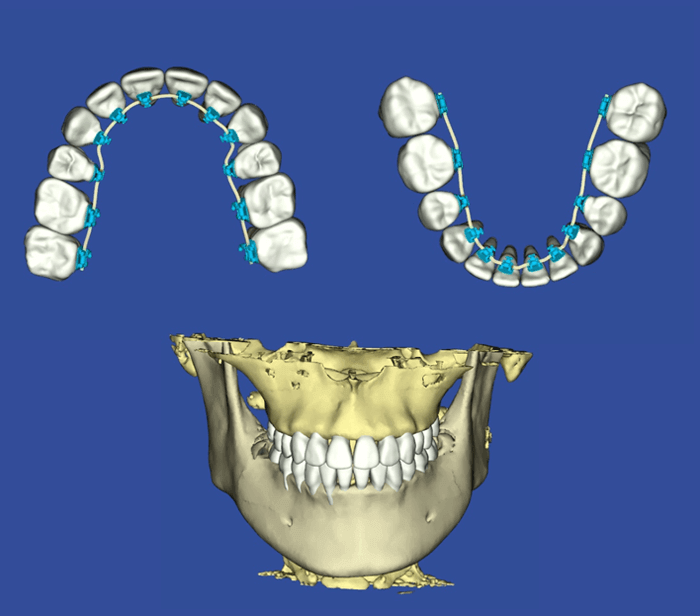

・3Dデジタル矯正システム!

矯正治療を得意とする日本橋はやし矯正歯科では、従来の矯正治療とは異なる「デジタル矯正システム」という最新の治療法を導入しています。

デジタル矯正システムを使用すれば、口の中をスキャンして患者さんごとに「ヴァーチャル・ペイシェント」と呼ばれる3Dの仮想患者さんを構築することができます。

そのヴァーチャル・ペイシェントを基に治療計画を決定していきます。さらに、その情報を基にしたカスタム矯正用ワイヤーの製作も可能。それぞれの患者さんに合わせた適切な矯正治療をデザインすることができます。

日本橋はやし矯正歯科では、歯だけではなく「歯根」や「あごの骨」までも3Dでモデル化します。そうすることによって、より安全性や効率性の高い歯科矯正装置による矯正治療を施すことができます。